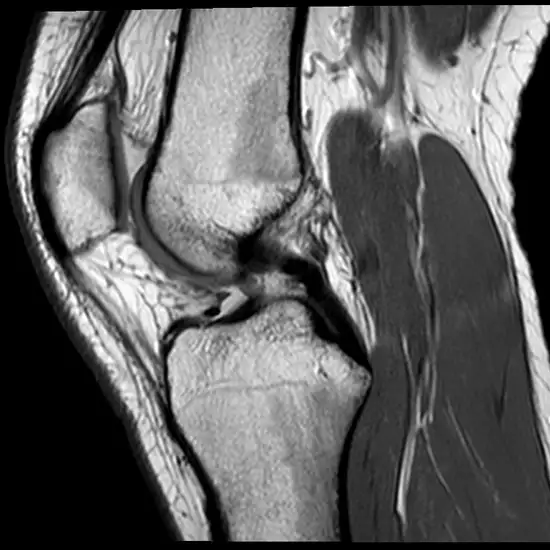

The bones, cartilage, tendons, ligaments, muscles, and blood arteries of the knee joint are visible on an MRI scan. The contrast enhances the MRI's sensitivity and diagnostic accuracy by enhancing the visibility of inside organs.